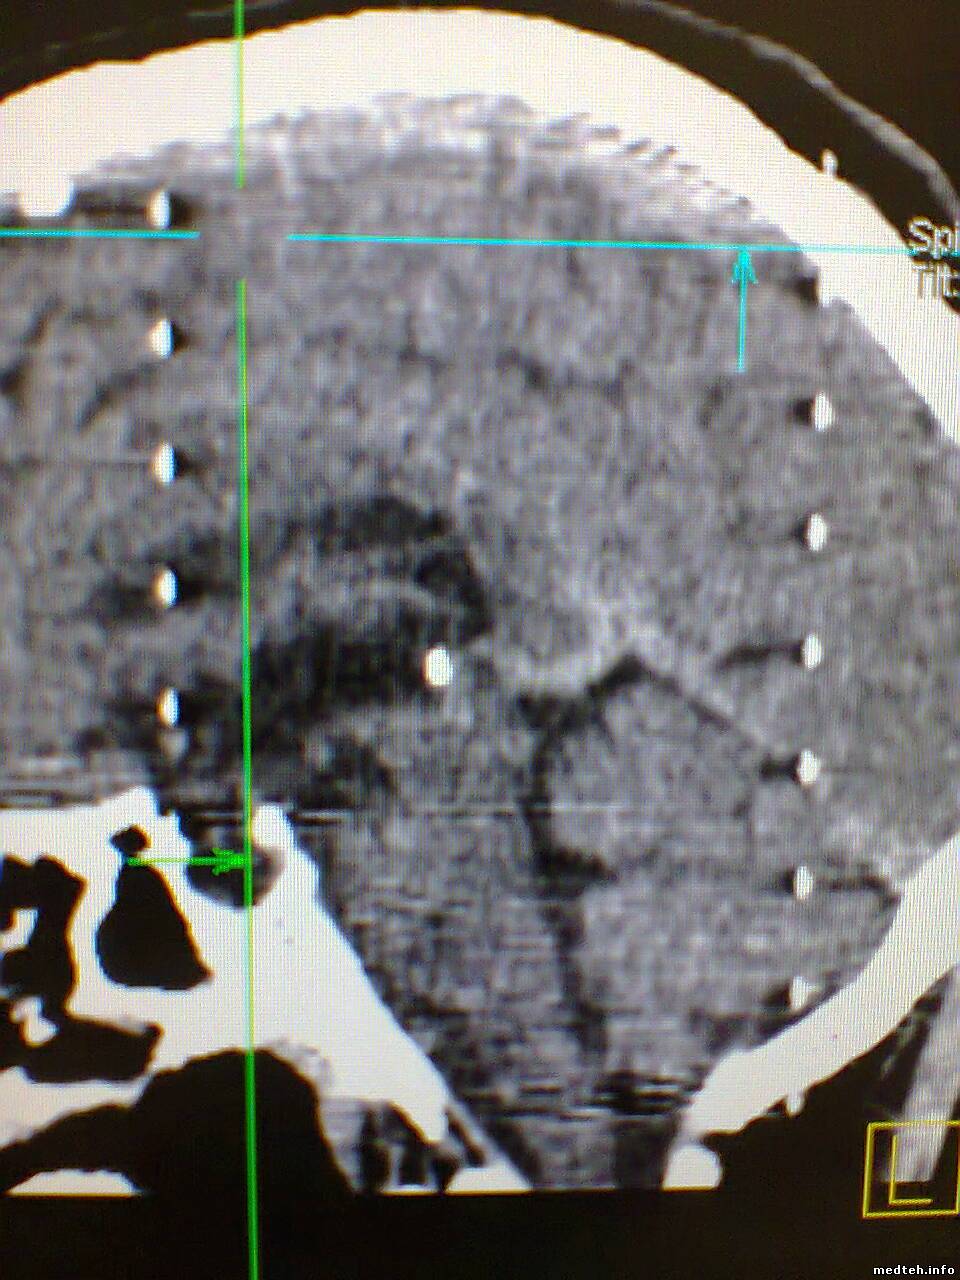

Доброго времени! Столкнулся с артефактом который появляется переодически ошибки при этом не даёт . Кто что думает...?

1982181.jpg (228.6 Kb) · 1606727.jpg (311.5 Kb) · 4363118.jpg (258.9 Kb)